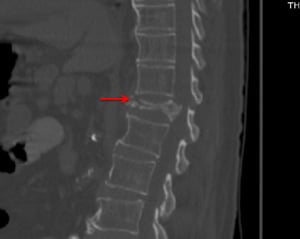

Diese CT-Aufnahme (sagittale Ansicht) zeigt eine ausgeprägte Kompressionsfraktur von T12 mit einer leichten degenerativen Erkrankung (z. B. Osteophyten im vorderen Wirbelkörper) an anderer Stelle.

Diese CT-Aufnahme (sagittale Ansicht) zeigt eine ausgeprägte Kompressionsfraktur von T12 mit einer leichten degenerativ

© Springer Science+Business Media